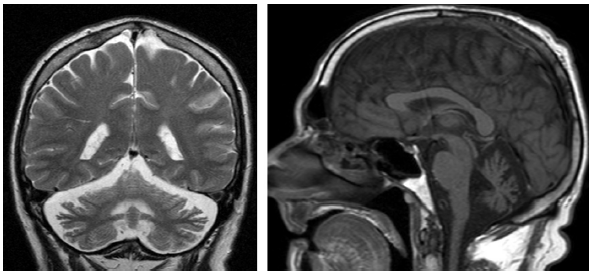

同时存在小脑性共济失调和自主神经功能障碍的主要原因是多系统萎缩(图 7),典型表现是桥脑出现“十字征”(图 8)。

图7 小脑型多系统萎缩。头颅MRI T1加权序列矢状位图像显示明显的小脑萎缩。

图8 多系统萎缩的“十字征”。图为头颅MRI FLAIR序列图像。十字征高信号是脑桥中缝核和脑桥小脑纤维的神经元丢失所致。

遗传性共济失调

表5总结了四种遗传性共济失调,这四种遗传性共济失调均很常见小脑萎缩。图9显示的是痉挛性共济失调相关的小脑萎缩。图10显示的是线粒体疾病相关的小脑萎缩。运动障碍如震颤和Kayser-Fleischer环的存在应考虑Wilson病(图11)。大多数SCA可见进行性橄榄小脑萎缩(图12和13)。

图9 头颅MRI显示痉挛性共济失调(ARSACS

)相关的小脑萎缩。左:头颅MRI T2加权序列冠状位图像; 右:头颅MRI T1加权序列矢状位图像。